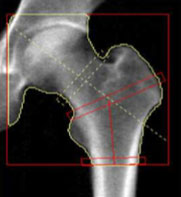

大腿骨頚部測定

大腿骨頚部(足の付け根の骨)は骨密度が低下していると、転倒した時に骨折しやすい部位です。骨折により寝たきりの原因になるため、注意が必要な部位です。

*測定時は足を少し内股にするために、固定具で足首を軽く固定させていただきます。